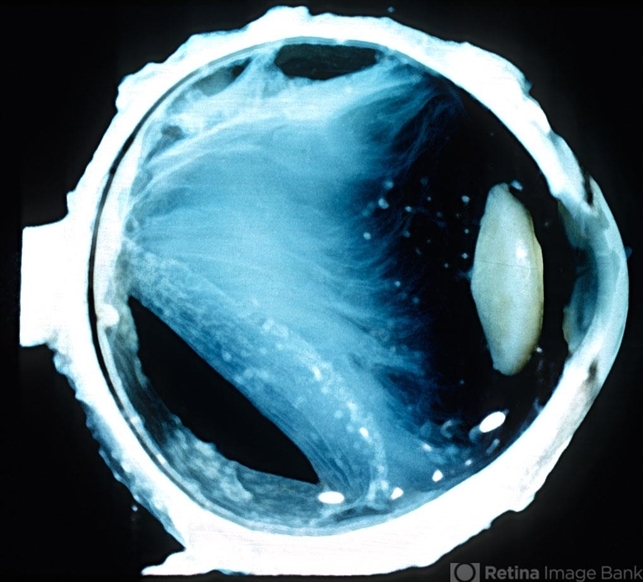

- vitritis, gross pathology

- Gross pathologic specimen showing vitreous organization and opacities consistent with severe intraocular inflammation.